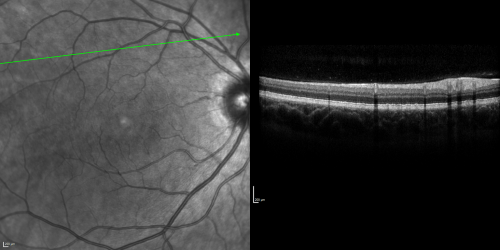

Basal Laminar Drusen - Cuticular Drusen - 19 Year Old with Lupus Nephritis

19-year-old.  She has a history of developing severe systemic lupus erythematosus in 2001.  She was in renal failure and had biopsy proven Class 2 lupus nephritis.  She is currently on Plaquenil 400 mg for six years, as well as Prednisolone orally, every other day. OD 20/20, OS 20/25.